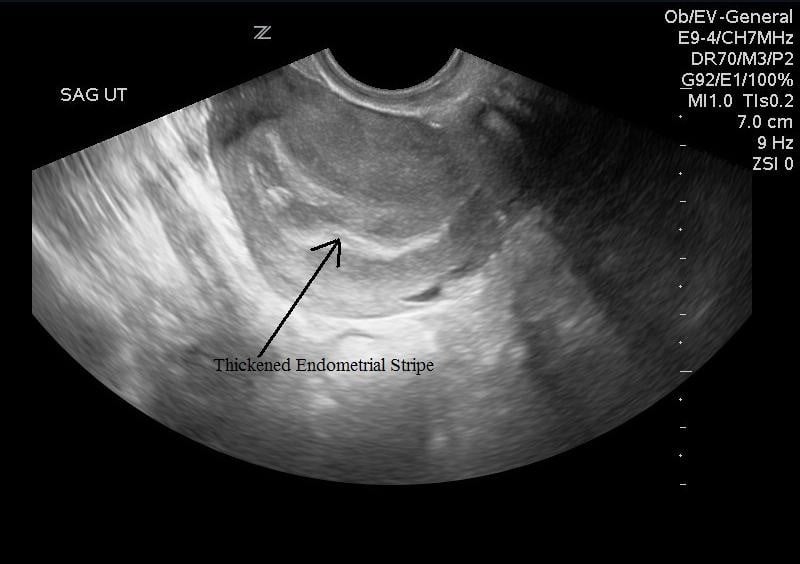

- In the transverse plane use the bladder as an acoustic window to identify the uterus. Fan all the way through by angling the beam towards then head and fan towards the feet. The endometrial stripe should be a hyperechoic line in the middle of the uterus.

- Insert or have the patient insert the probe into the vagina with probe indicator towards to ceiling. This is the sagittal/longitudinal plane. (Illustrations 7 and 8)

- Illustration 8. Image of transvaginal sagittal/longitudinal view. Notice hyperechoic (bright) endometrial stripe.